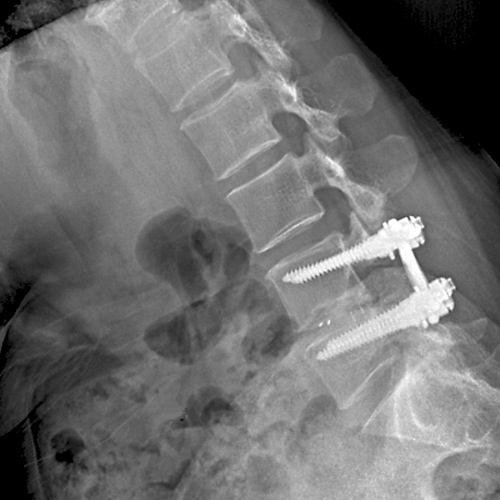

척추관 협착이나 기타 변형으로 인해 불안정한 척추를 스크류로 안정화시켜 수술 후 조기 보행과 유합율을 높여 줍니다.

협착증이 있는 부분에 요추 후궁절제술로 척수신경을 충분히 풀어 준 다음에 척추의 불안정증을 교정하기 위하여 기구(스크류)를 이용하여 척추를 고정하는 수술입니다.

나사못과 금속 기구를 사용하여 불안정한 척추 분절을 단단하게 고정하고 유합시켜, 척추의 안정성을 영구적으로 확보합니다.

불안정하거나 퇴행된 척추 마디의 움직임을 제거하여, 해당 부위에서 발생하는 만성적인 통증을 근본적으로 해소하는 데 가장 효과적입니다.

나사못 고정과 함께 신경을 압박하는 구조물(인대, 뼈 등)을 충분히 제거하여 신경 통로를 넓히는 감압 효과를 극대화합니다.